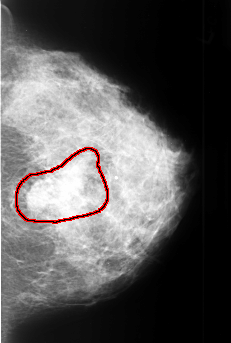

B_3409_1.LEFT_CC

LEFT_CC LINES 4456 PIXELS_PER_LINE 3000 BITS_PER_PIXEL 12 RESOLUTION 50 OVERLAY

FILE: B_3409_1.LEFT_CC.OVERLAY

TOTAL_ABNORMALITIES 1

ABNORMALITY 1

LESION_TYPE MASS SHAPE LOBULATED-IRREGULAR MARGINS OBSCURED-ILL_DEFINED

ASSESSMENT 4

SUBTLETY 4

PATHOLOGY MALIGNANT

TOTAL_OUTLINES 1

BOUNDARY